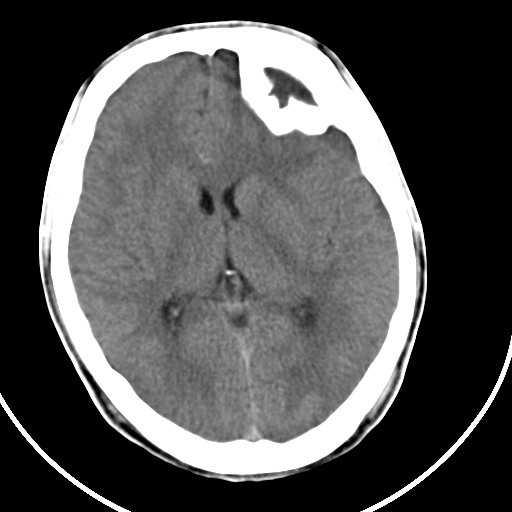

标题: CT21939:男20岁,外伤一年后,现头疼. [打印本页]

标题: CT21939:男20岁,外伤一年后,现头疼.

颅骨凹陷性骨折并压迫脑组织致大脑镰下疝!

是硬膜外血肿机化还是陈旧性凹陷性骨折?

硬膜外血肿机化

结合文献报道,考虑血肿继发改变,血肿骨化?

如果是骨折,外板正常内板这么明显凹陷,请问这样的骨折是怎样形成的?形成的机理是什么?有没有可能形成?

硬膜外血肿伴包膜钙化

左侧额部硬膜外血肿机化、骨化。

左侧额部硬膜外血肿机化、骨化